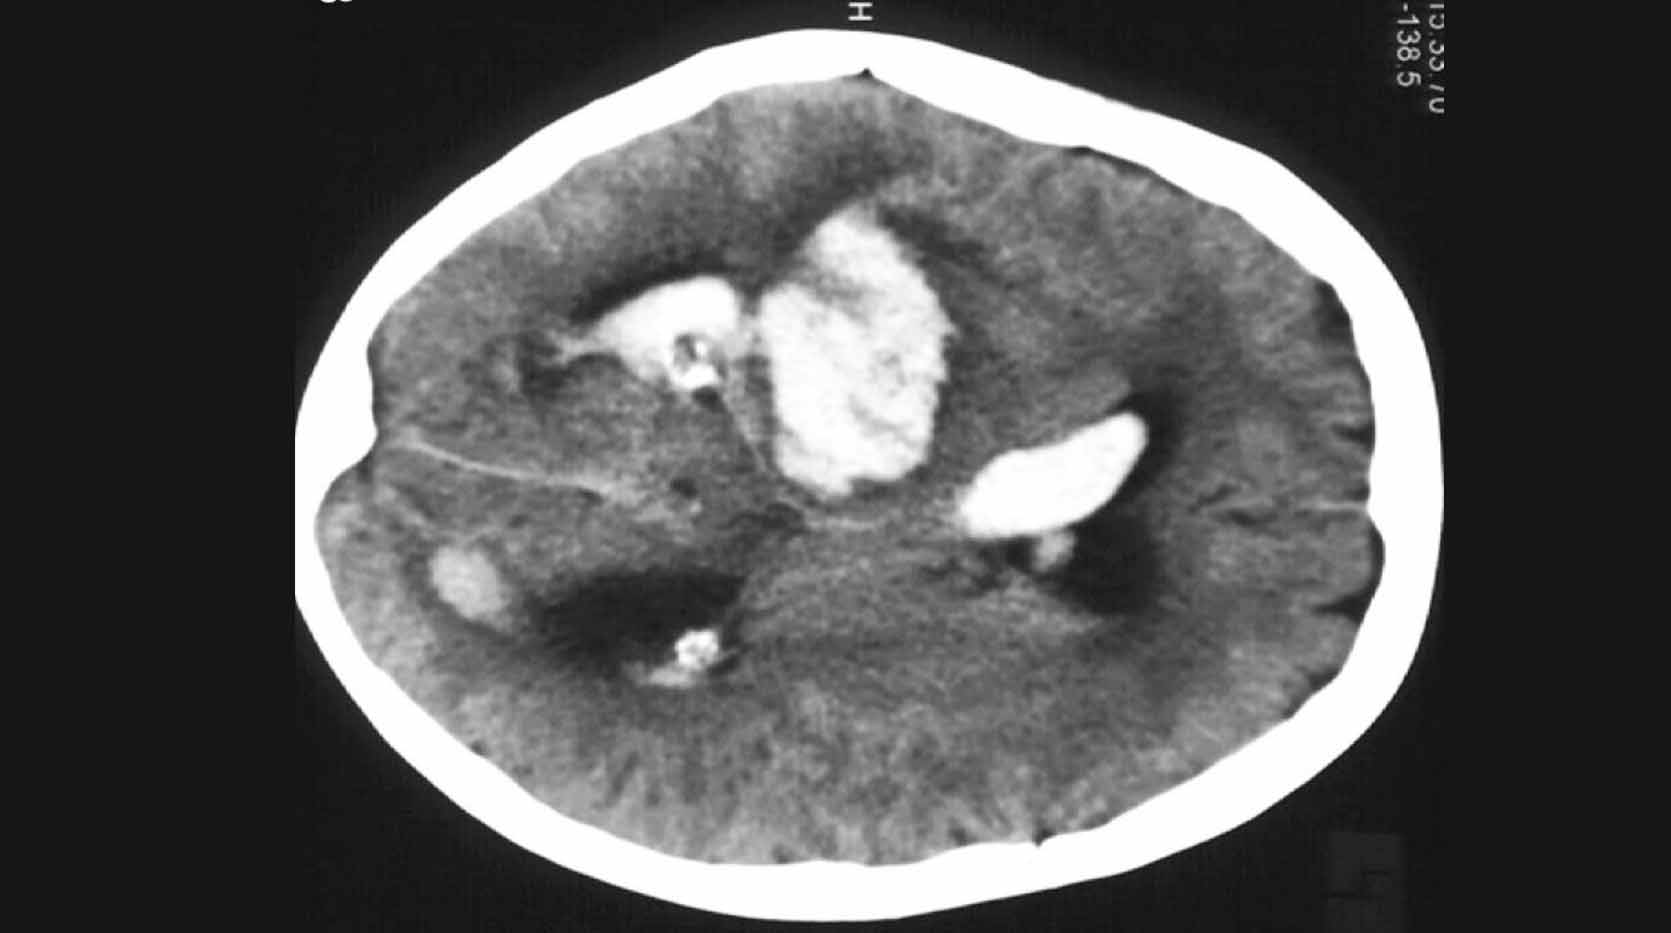

hemorragia cerebral Puede deberse a un trauma cerebral. The following 2 files are in this category, out of 2 total. Media in category intracerebral hemorrhage. La causa suele ser la hipertensión. Puede ser externo o dentro del cuerpo. Como ya se ha mencionado, suele estar relacionada con la hipertensión. Un hematoma intracraneal es una acumulación de sangre dentro del cráneo. En general, se distinguen entre hemorragias profundas (incluyendo aquellas que afectan a núcleos grises profundos de los hemisferios cerebrales), hemorragias.

Hemorragia Intracerebral subraquídea Neurocirugía de la Torre